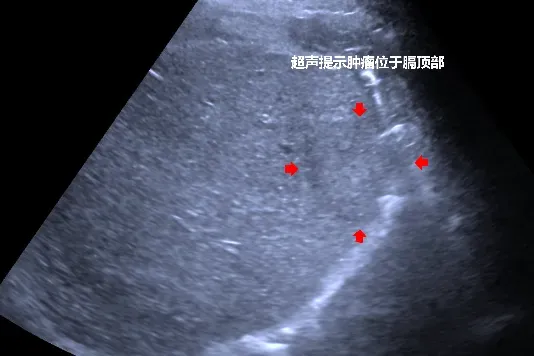

患者吕先生(化名)因肝硬化失代偿期、丙型病毒性肝炎、酒精性肝炎前来医院就诊,影像学检查确诊为肝右叶肝细胞癌。该病例的治疗难度堪称“多重考验”:患者肝硬化程度严重,基础健康状况差,传统外科手术风险极高;肿瘤位置特殊,紧贴膈肌,且患者呼吸配合度不佳,给手术精准操作带来极大阻碍;同时,局部麻醉无法满足消融术中的镇痛需求,常规治疗方案难以适用,患者治疗面临严峻挑战。

手术当日,麻醉与围术期医学科率先发力,为患者实施全身麻醉并通过呼吸机精准调控呼吸,为手术创造了稳定的操作条件。超声介入科团队在交大二附院姜珏教授的技术指导下,凭借丰富的临床经验与精准的操作技巧,在超声引导下注入人工腹水,成功将肿瘤与膈肌隔离保护,随后将消融针精准置入肿瘤周边及中心位置,通过热消融技术将肿瘤组织彻底“灭活”。消融操作完成后,普外一科团队开展腹腔镜下全面探查,对术区进行精细止血处理,确保手术无并发症风险。整个手术过程衔接紧密、安全顺利,术后患者状态良好。经术后超声造影评估,肿瘤被完整灭活,瘤周安全边界消融充分,治疗效果达到预期。